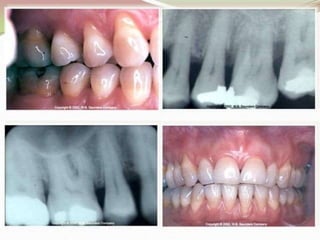

Periodontics is a branch of dentistry focused on diagnosing and treating conditions and diseases affecting the supporting and surrounding tissues of teeth. The field addresses issues such as periodontitis, which is inflammation of the periodontal structures. The document introduces key concepts related to periodontics.